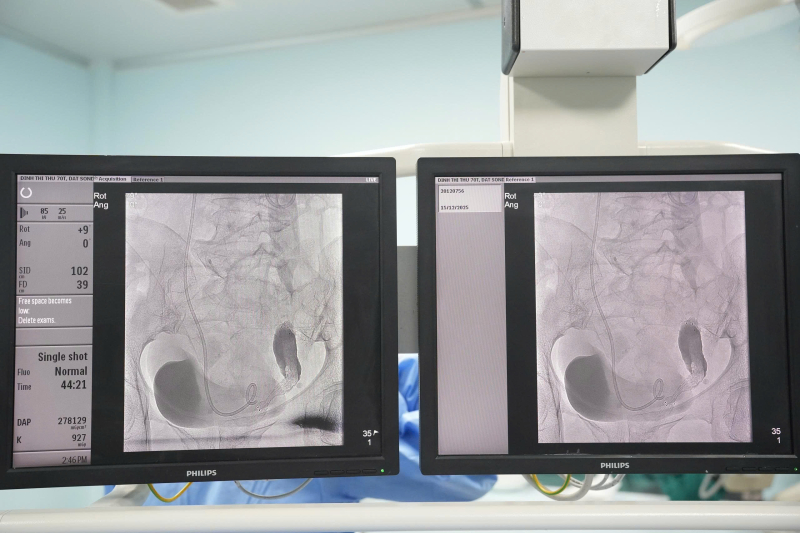

Hình ảnh: stent niệu quản trên hệ thống chụp mạch số hóa xóa nền (DSA).